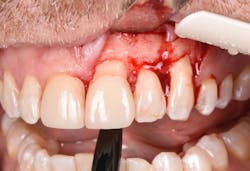

Figure 22: A regenerative approach was taken using a xenograft bone graft in combination with BB human recombinant platelet-derived growth factors.

Purchasing the Er:YAG laser can be beneficial to clinicians who desire a true hard- and soft-tissue laser. The amount of training is minimal, and the settings are similar for various applications. Since the Er:YAG laser has an affinity to water, it has been shown to have minimal thermal changes, and it promotes reduced postoperative discomfort. One study showed that when cutting bone for partially erupted third-molar extractions, not only less intra- and postoperative pain was noted, but also a reduction in facial swelling when compared to conventional bur drilling.13

Figure 23: A porcine 3-D volume stable collagen matrix was used not only as a barrier but also to enhance the thickness of the soft tissue. The matrix thickness measured 3 mm to achieve gingival horizontal volume.

Figure 24: Immediate post-op of gingival tissue repositioned tension-free.

Figures 25 and 26: One-year postsurgery. Clinically all signs of retrograde peri-implantitis have been eliminated and radiographic bone fill can be seen.